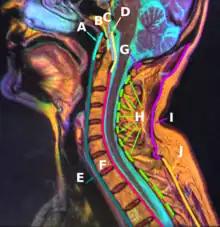

I: Nuchal ligament